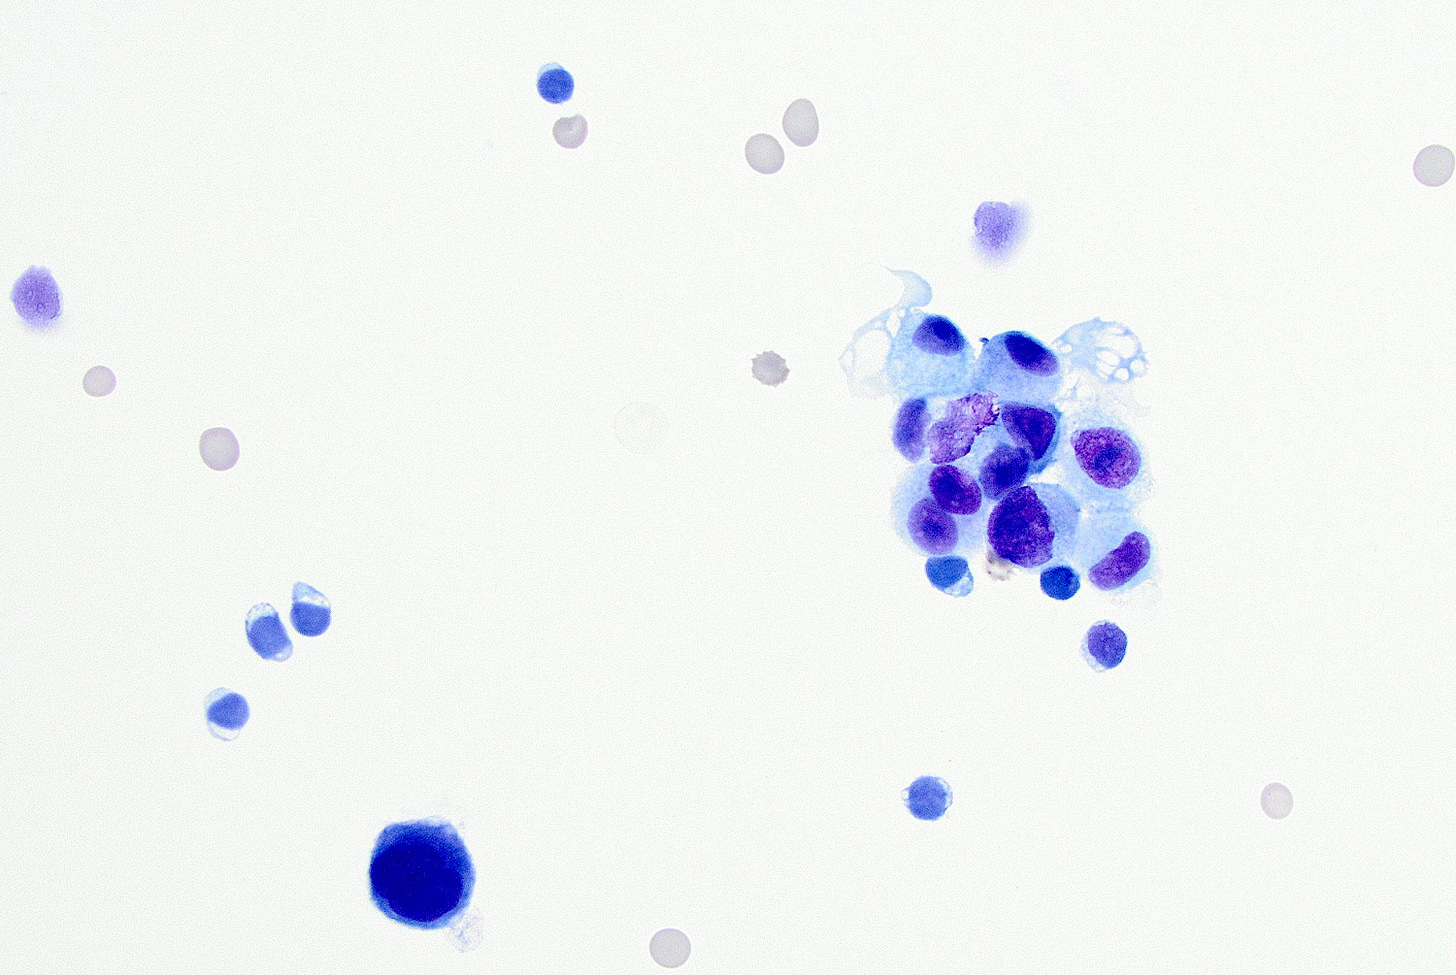

As shown below, LCIS is characterized by a lobulocentric proliferation of cells that expand lobular units. The LCIS cells are uniform, loosely cohesive and evenly spaced (“marbles in a bag”). They are slightly larger than normal breast epithelial cells, with indistinct cell borders and pale cytoplasm. Two types may coexist. Type A LCIS cells have small to slightly enlarged, uniform, round nuclei with inconspicuous nucleoli. Type B cells have larger nuclei, more abundant cytoplasm and more prominent nucleoli.

Classic LCIS - microscopic images